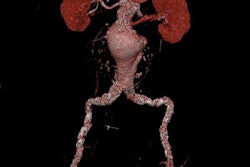

SPECT/CT image of a 35-year-old woman with a small bile leak at the cholecystectomy site. Image courtesy of Dr. Elham Safaie.The average additional scan time for SPECT/CT ranged from 20 to 30 minutes, depending on the patient's dose and his or her situation, Safaie said. That added scan time is "reasonable even in an emergency setting," she added.